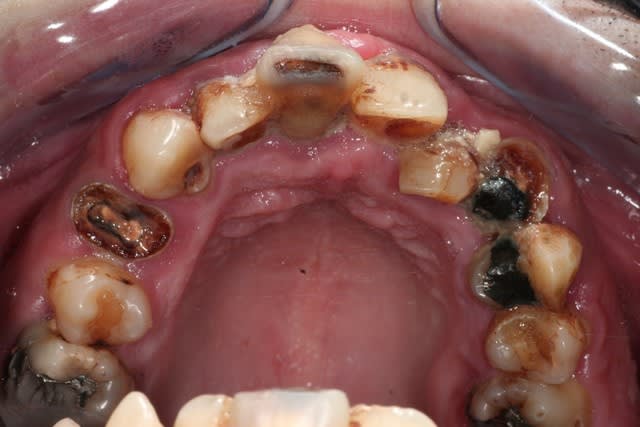

lâchez vous.

je crois que là, à part dentisterie véto et pédo, tu as tous les thèmes d'eugénol dans une seule bouche.

j'explique le contexte: jeune homme à l'adolescence plutôt difficile, rangé des voitures. s'est mis à son compte.

hyper motivé, à souscrit un crédit pour la totalité des travaux. on démarre dans quinze jours si tout va bien.

va t y sermoner sur l'hbd? grrr... avec delicatesse surement, parceque le jeune homme a visiblement passé beaucoup de temps chez les dentistes, beaucoup de séances, et le resultat...

mais je parie que la matière va stimuler l'artiste, il y a de quoi faire une belle bouche et ce sera surement le meilleurs outil de motivation

ensuite comment la mécanique alhounienne va t elle s'epanouir et se révéler? par exemple, mais entre autre, va t y se bagarrer avec cette 34 en reprenant l'endo et en esperant resurrection (c'est jouable), va t y virer et implanter avec le reste (il y a tellement d'os si tentant)? comment l'endo qui est au plus profond de lui va t il se confronter avec l'implanto encore plus enfoui?

4 implants ( ? ) et hausse de la DVO. mais avant decouverte du brossage.

Au delà du problème de brossage, le résultat est probablement surtout dû à de l'héroïne en IV, donc si le mec est vraiment guéri (est-ce que c'est seulement possible ?) de son addiction, pourquoi pas ?